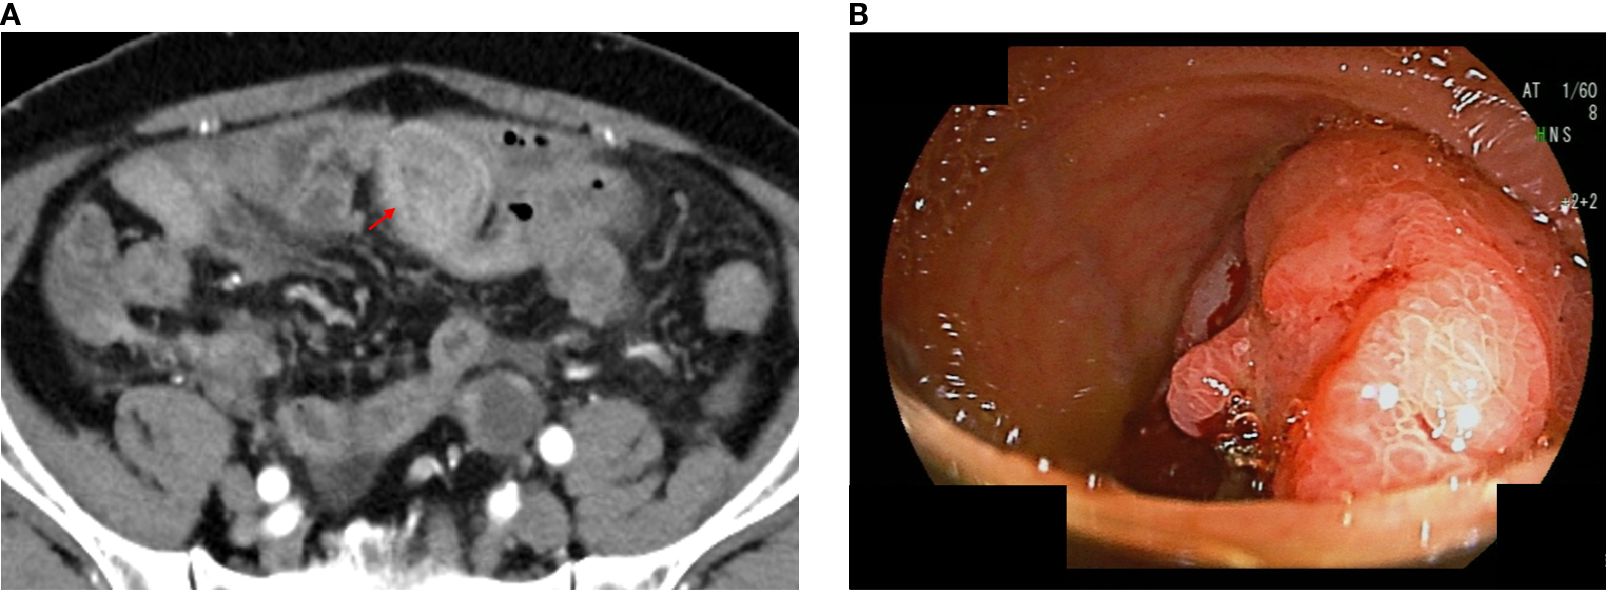

A 74-year-old man presented at another hospital for abdominal bloating. His past medical history included bladder cancer, for which he underwent transurethral resection of bladder cancer at age 69, with a final pathological stage of pStage 0a (TaN0M0 according to the TNM Classification of Malignant Tumours, 9th edition), low grade. The laboratory tests were essentially normal, except for an elevated serum carcinoembryonic antigen (22 ng/mL) and carbohydrate antigen 19-9 (2,073 ng/mL). Contrast-enhanced computed tomography (CT) revealed multiple pulmonary nodules, peritoneal dissemination, mesenteric lymphadenopathy, ascites, and an enhanced mass lesion in the ileum with a 35-mm diameter (Figure 1). The patient was subsequently referred to our hospital for further evaluation.

Figure 1

CT scan of the abdomen (Panel A) shows a highlighted area with a red arrow indicating a mass. Endoscopic view (Panel B) shows a polypoid lesion in the intestinal lining.

Figure 1. Computed tomography (CT) and endoscopic images of unresectable Meckel’s diverticulum cancer. CT images performed at our hospital; the arrow indicates an enhanced mass lesion in the ileum (a). Double-balloon endoscopic finding of Meckel’s diverticulum cancer (b).

Transanal double-balloon endoscopy revealed an irregular ulcer at the top with a marginal swelling (Figure 1), and its histological examination revealed a well-differentiated adenocarcinoma adjacent to areas of ectopic gastric epithelium (Figure 2). Immunohistochemistry of the tumor cells revealed positivity for MUC5AC and MUC6 and negativity for MUC2 and CDX2 (Figure 2). Esophagogastroduodenoscopy did not reveal any primary gastric cancer. A retrospective review of previous CT images revealed the presence of a Meckel’s diverticulum. The tumor was therefore concluded to have originated from ectopic gastric epithelium within a Meckel’s diverticulum.